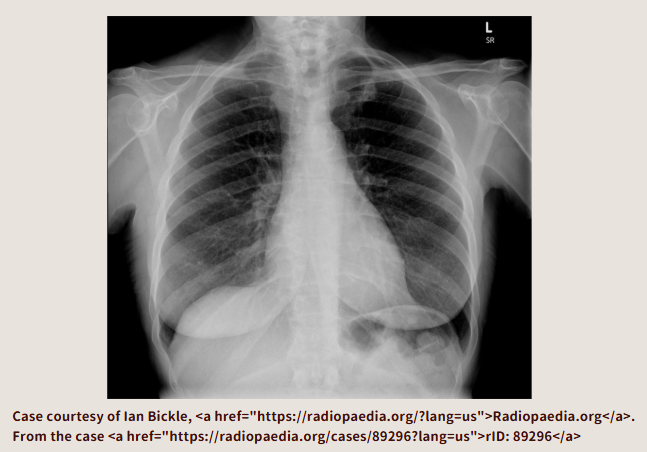

左肺尖部、あやしいかな。

肋骨の断端かな? 結節影?

結局CT撮るんですよ。呼吸器内科の先生だって結局CT撮るんですよ。だったら、今日内科でCT撮ったほうがいいでしょう。何もなければ今日で終了です。あやしい影があったら、読影に出して(呼吸器内科の先生も読影があったほうがうれしいでしょう)呼吸器内科外来を予約してあげましょう。